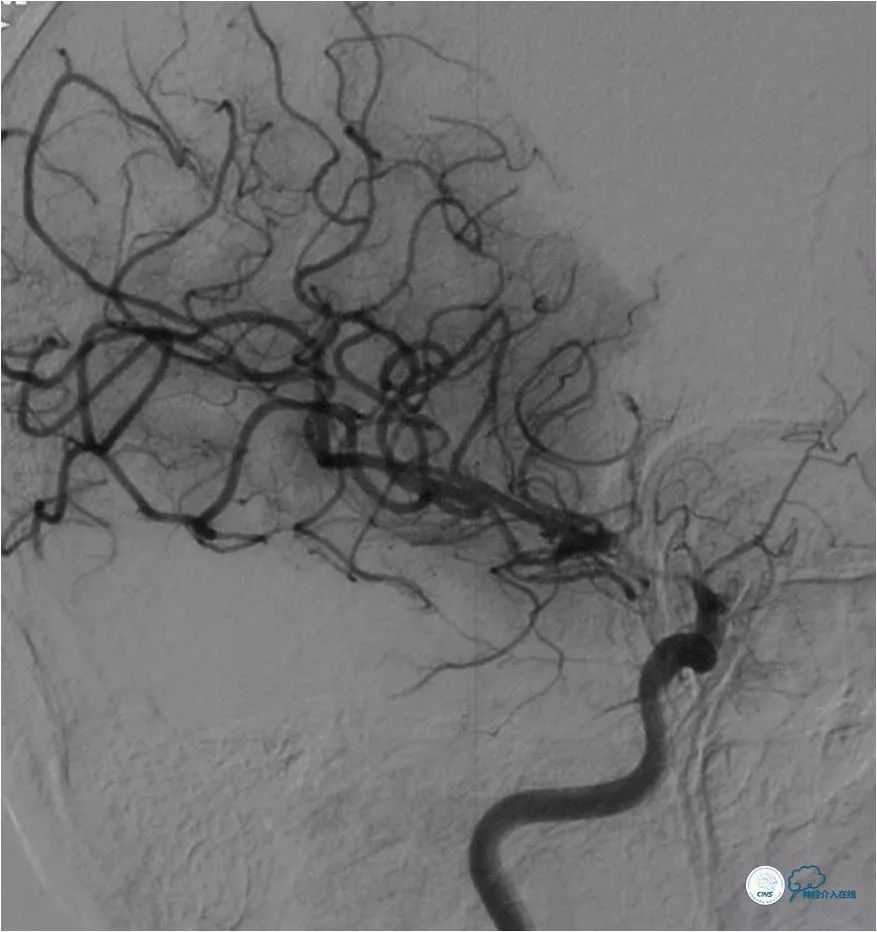

DSA(2018-6-1):右颈内动脉C7段重度狭窄,右颈内动脉系孤立颈动脉系统,右大脑前动脉A1段发育不良或者缺如。前交通动脉开放,见右大脑前动脉经软脑膜动脉向右大脑中动脉供血区域代偿。未见明显后循环参与代偿(图3-5)。

图3

图4

图5